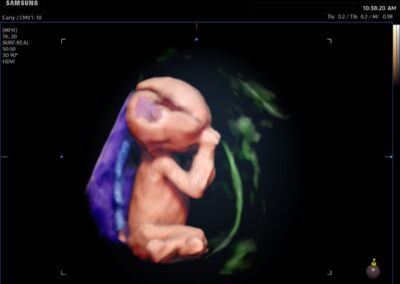

Comprehensive, advanced and expert MFM care for high-risk pregnancies

- Fetal anomalies